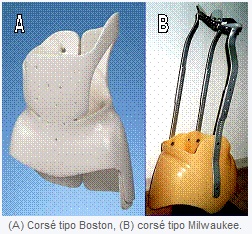

Dado que los tratamientos para la escoliosis sólo son para detener la progresión y no reducir los grados ya presentes, cuanto antes se aplique el tratamiento, menos grados tendremos al final del crecimiento. El uso de corsés conlleva mucha controversia dado que su efectividad no ha sido adecuadamente investigada (1, 2, 3).El corsé se empieza a aplicar generalmente cuando ya ha progresado la escoliosis a 20º, por lo que tampoco hace nada por detener la progresión antes de llegar a 20º.Otro problema es la constancia en su uso debido a la incomodidad física y aversión psicológica que provoca en un adolescente que lo tiene que llevar todo el día.